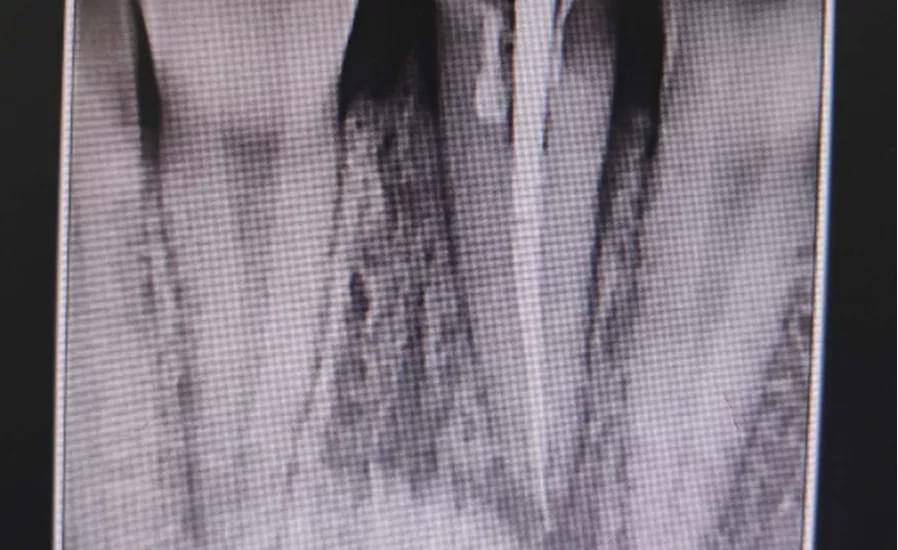

“经检查,患者患牙冠冠根联合折,折断面位于龈下2mm,患牙唇侧倾斜,缺牙间隙较大,拍片检查患牙牙根长度尚可,残留牙根未见明显折断,还有机会可以让它恢复如初。”驻马店市中心医院口腔科值班医生杜驿明为患者完善检查后的一番话,让张女士心里有了重塑美丽的希望。

经过会诊,一致决定由杜驿明医生为患者完善根管治疗,王利民医生植入纤维桩,利用光固化树脂制作临时牙,刘小东医生行合向+腭向牵引牙根,同时关闭前牙间隙。

经过3个月的正畸治疗,张女士的门牙断面位于龈上,间隙消失,牙列整齐,完美的恢复了患者牙齿的美观,患者非常满意。